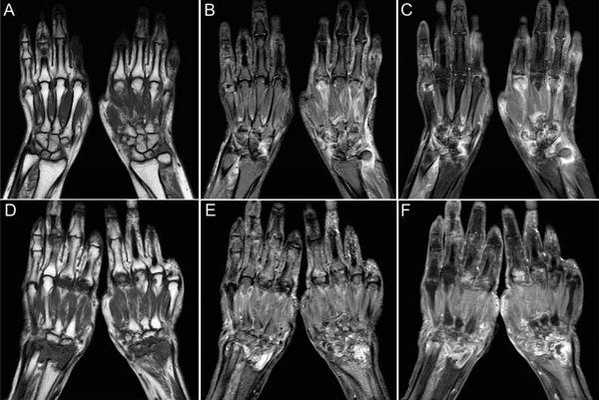

Рисунок проксимального межфалангового сустава в заднепередней проекции: признаки прогрессирующей деструкции.

(А) Нормальный сустав с интактными кортексом, хрящом, костной плотностью и капсулой.

(В) Показана ранняя стадия заболевания только с признаками синовита и выпота.

(С) Рисунок: юкстаартикулярная остеопения с размытым кортексом и штрих-пунктирным характером изменений.

(D) Рисунок: истончение хряща и краевые эрозии в той части кости, которая лежит внутри капсулы, но не покрыта хрящом.

(Е) Рисунок: признаки прогрессирующей остеопении и субхондральных эрозий, распространяющихся через дефекты хряща.

(F) Рисунок: признаки мутилирующего артрита с деформацией по типу «карандаша в стакане», наблюдающиеся в поздней стадии заболевания.